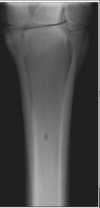

LateroMedial –> PROXIMAL METACARPAL

DorsoPalmar –> PROXIMAL METACARPAL

DorsoLateral-PlantoMedial Oblique –> PROXIMAL METACARPAL